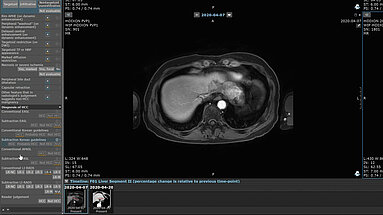

Recent advancements in MRI techniques and tumor biology have led to updated hepatocellular carcinoma (HCC) diagnostic guidelines from various liver study associations. Conducted across 11 South…